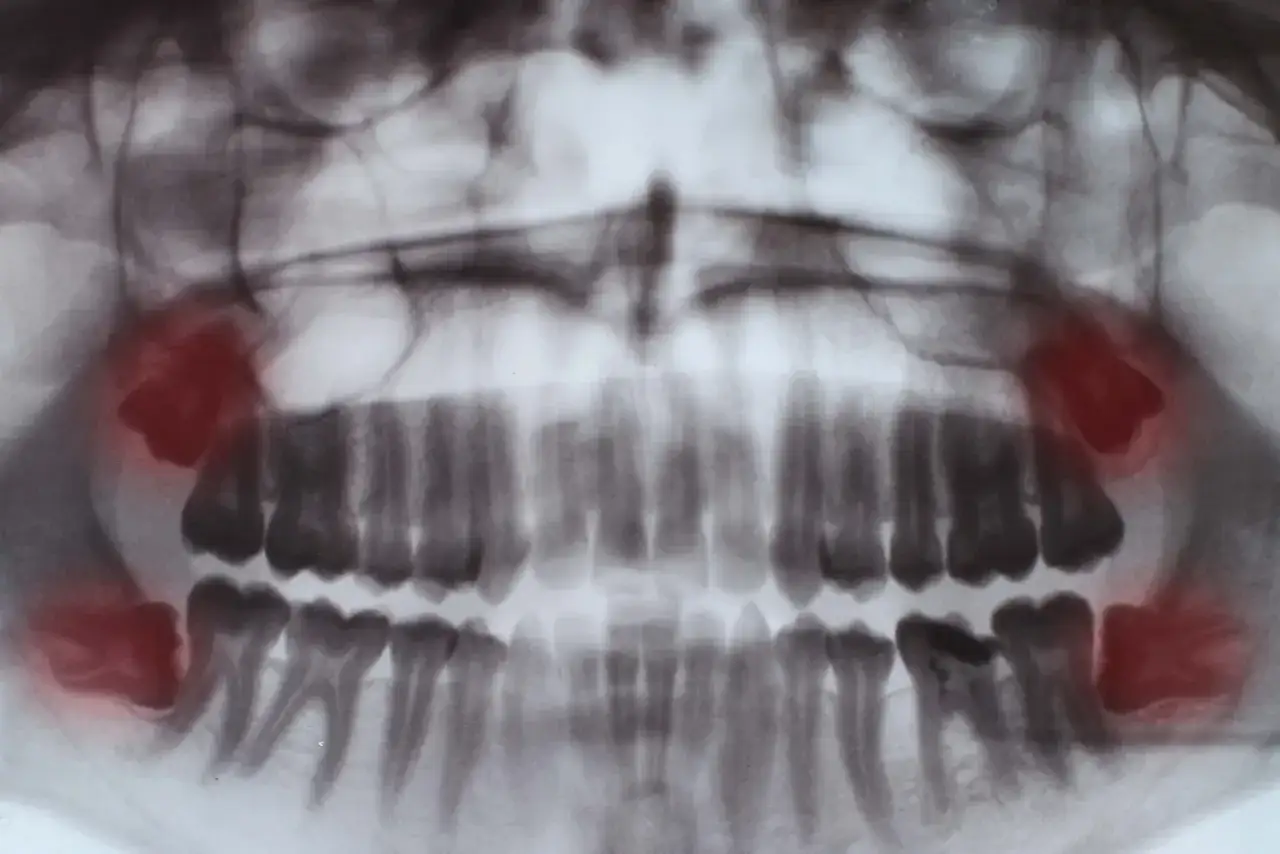

- Nie każdy ma zawiązki wszystkich zębów mądrości to cecha ewolucyjna, a ich obecność sprawdza się zdjęciem pantomograficznym.

Jednym z najczęstszych problemów jest tzw. ząb zatrzymany. Oznacza to, że ząb mądrości jest w pełni uformowany, ale nie może się przebić przez dziąsło i pozostał całkowicie w kości szczęki lub żuchwy. Taki ząb, choć niewidoczny, może stanowić poważne zagrożenie. Brak możliwości wyrznięcia się może prowadzić do rozwoju stanów zapalnych, bólu, a nawet uszkodzenia sąsiednich struktur kostnych i korzeni innych zębów.

Niewyrznięte zęby mądrości, zwłaszcza te zatrzymane, mogą prowadzić do rozwoju poważniejszych powikłań. Jednym z nich jest powstanie torbieli. Torbiel to jama wypełniona płynem, która rozwija się wokół zatrzymanego zęba. Z czasem może ona powiększać swoją objętość, niszcząc otaczającą kość szczęki lub żuchwy oraz korzenie sąsiednich zębów. Dodatkowo, trudności w utrzymaniu higieny wokół ósemek znacząco zwiększają ryzyko rozwoju próchnicy, zarówno na samym zębie mądrości, jak i na sąsiednich zębach. Regularne kontrole stomatologiczne pozwalają na wczesne wykrycie tych zagrożeń.